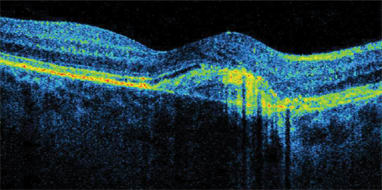

SDOCT does not skip or miss data points, as time domain OCT does because of its speed limitations. Thickness data between time domain scan lines is not actually measured, and values must be interpolated. No interpolation is needed with SDOCT. "We can see pathology that time domain OCT would have missed," Dr. Sharma says. "For example, SDOCT detects drusen or areas of subretinal fluid (Figure 1) that would have fallen between scans on time domain OCT. Also, it is much easier to discriminate pathology with SDOCT technology. For example, it is easier to discern the presence or absence of epiretinal membranes." (Figure 2)

Figure 2. An epiretinal membrane imaged by the Copernicus.